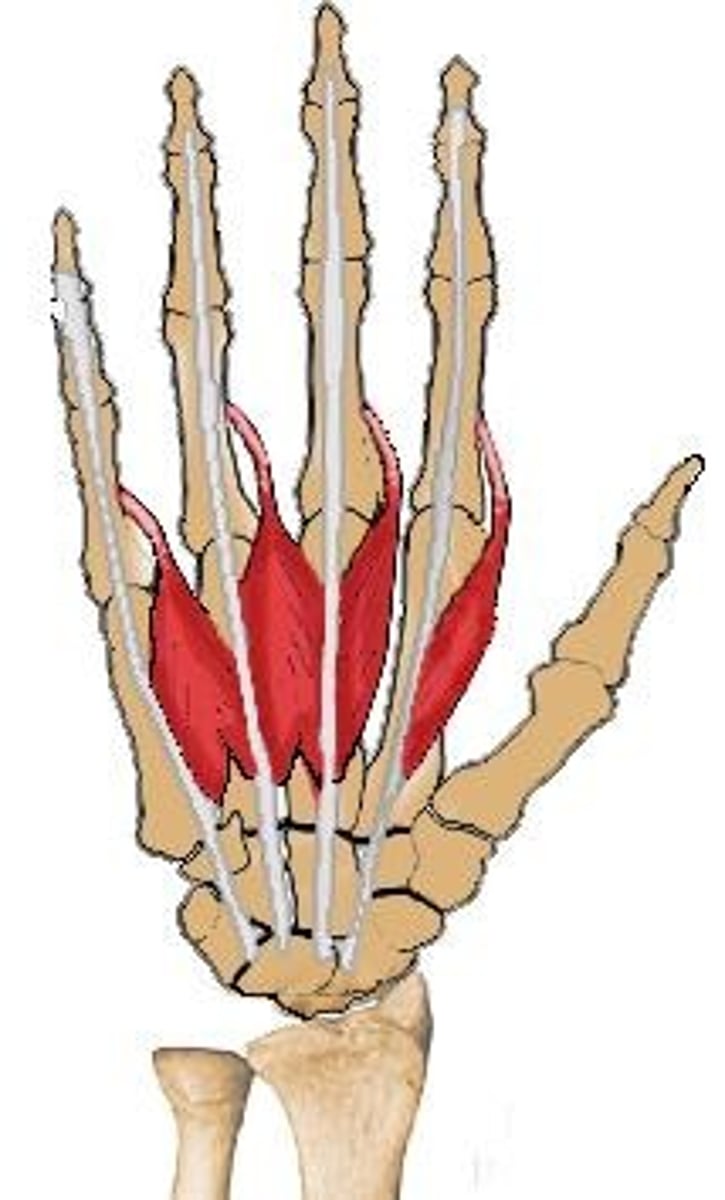

Lumbricals

palmar interosseous

dorsal interosseous